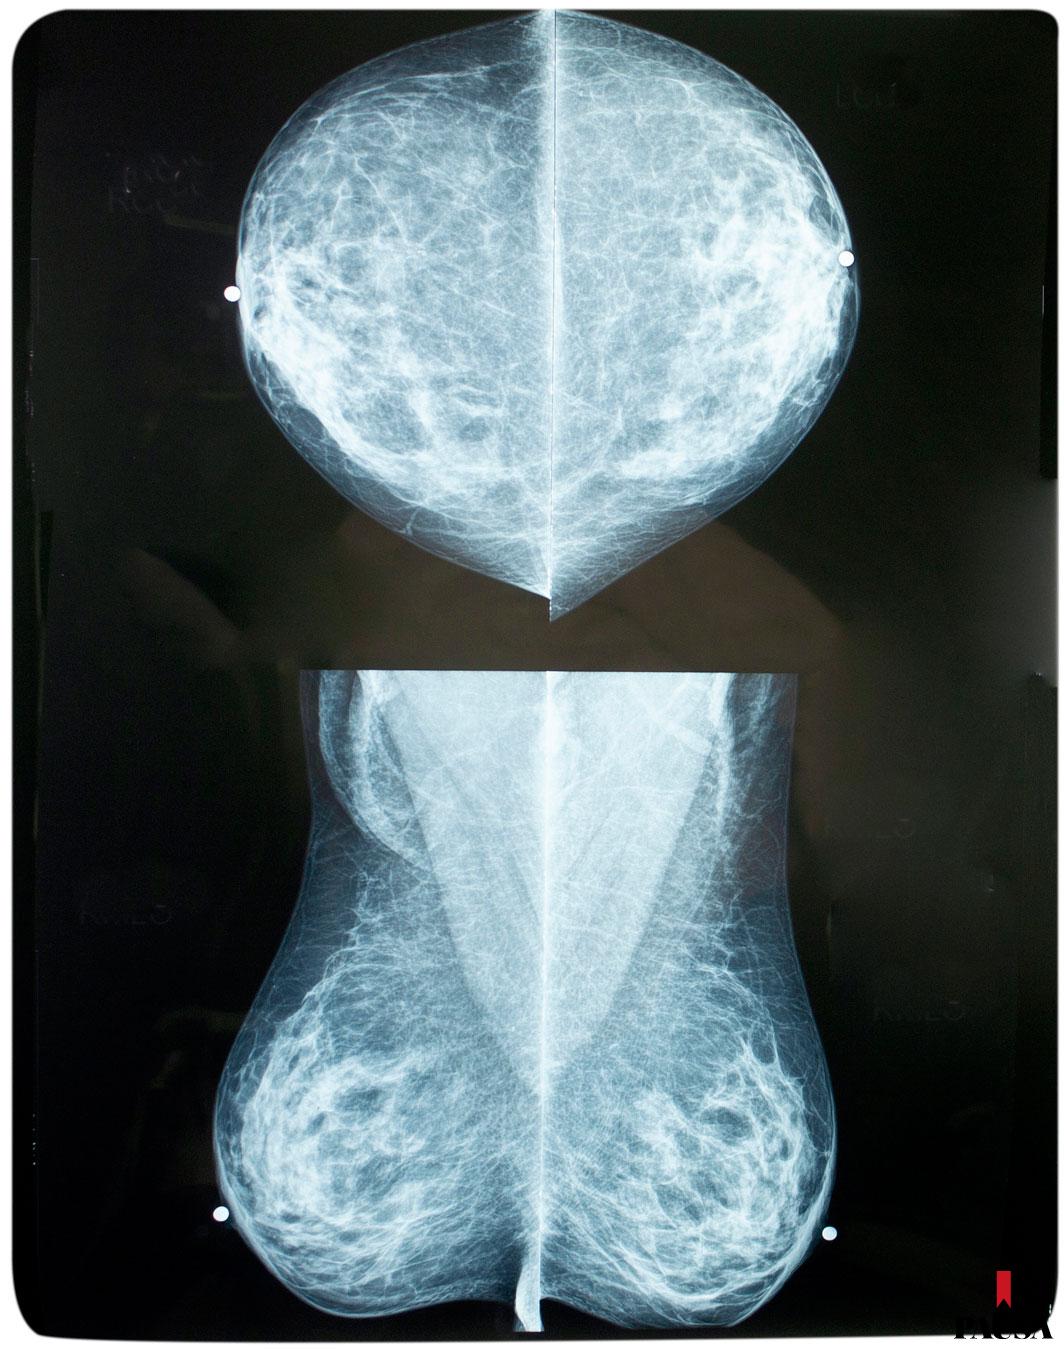

El de mama es el tipo más común de cáncer entre las mujeres en Paraguay y la principal causa de muerte en la población femenina. Durante el 2023, el Instituto Nacional del Cáncer (Incan) diagnosticó más de 600 nuevos casos y registró 274 fallecimientos a nivel nacional. Estas cifras alarmantes evidencian la necesidad de tomar medidas urgentes en la detección temprana y la prevención de esta enfermedad.

En Paraguay, 24 servicios de salud distribuidos en 12 regiones sanitarias cuentan con mamógrafos en funcionamiento, y 19 de estos centros ofrecerán horario extendido durante octubre. En esta nota, compartimos información recopilada por el Programa Nacional de Prevención, Detección Precoz y Tratamiento del Cáncer de Cuello Uterino y Mama, dependiente del Ministerio de Salud Pública (MSP).